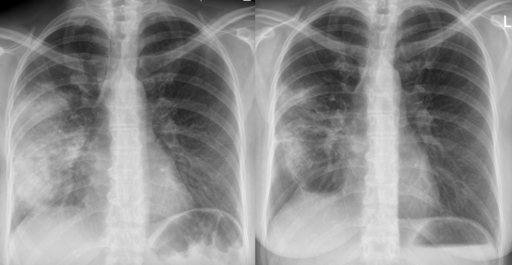

Röntgenaufnahme der Brust

Eine definitive Diagnose der CAP erfordert den Nachweis einer Konsolidierung auf einer Röntgenaufnahme des Brustkorbs (CXR). Daher wird empfohlen, bei allen Patienten, die ins Krankenhaus eingeliefert werden, so schnell wie möglich eine Röntgenaufnahme des Brustkorbs zu machen, idealerweise innerhalb von 4 Stunden nach der Aufnahme.

Röntgenbild einer Lungenentzündung vor (links) und nach (rechts) der Antibiotikatherapie

Akute Lungenentzündung

Hellerhoff, CC BY-SA 3.0, über Wikimedia Commons